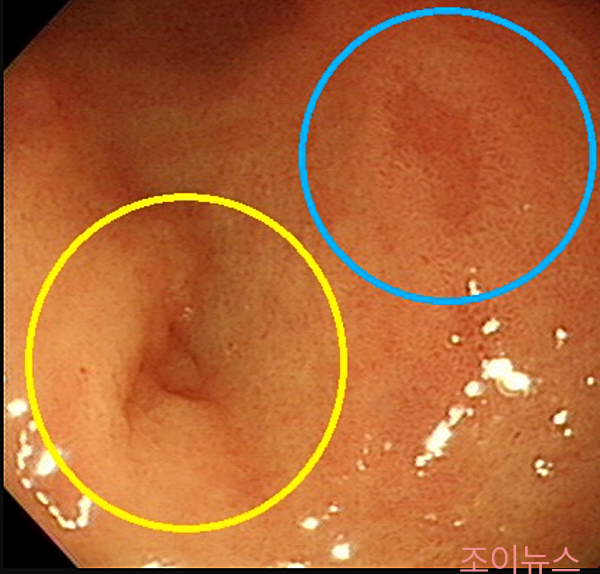

미란성 위염

- 위 점막에 얕은 상처(미란)가 생기는 위염입니다.

- 스트레스, 약물, 헬리코박터 파일로리균 감염 등으로 인해 발생합니다.

- 속 쓰림, 소화불량, 복통, 메스꺼움, 출혈 등의 증상이 나타날 수 있습니다.

- 원인에 따라 헬리코박터 파일로리 제균 치료, 위산 분비 억제제, 점막 보호제 등을 사용하여 치료합니다.

- 스트레스 관리 및 생활 습관 개선이 매우 중요합니다.